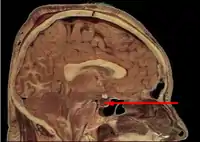

Mesal aspect of a brain sectioned in the median sagittal plane.

![]() Median sagittal through the hypophysis of an adult monkey. Semidiagrammatic. | |